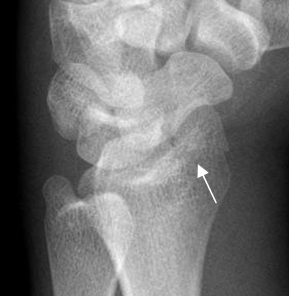

Fig 37. Fractura de Barton volar.

Rx oblicua. Fractura intra-articular y en sentido oblicuo, en la parte anterior del radio.